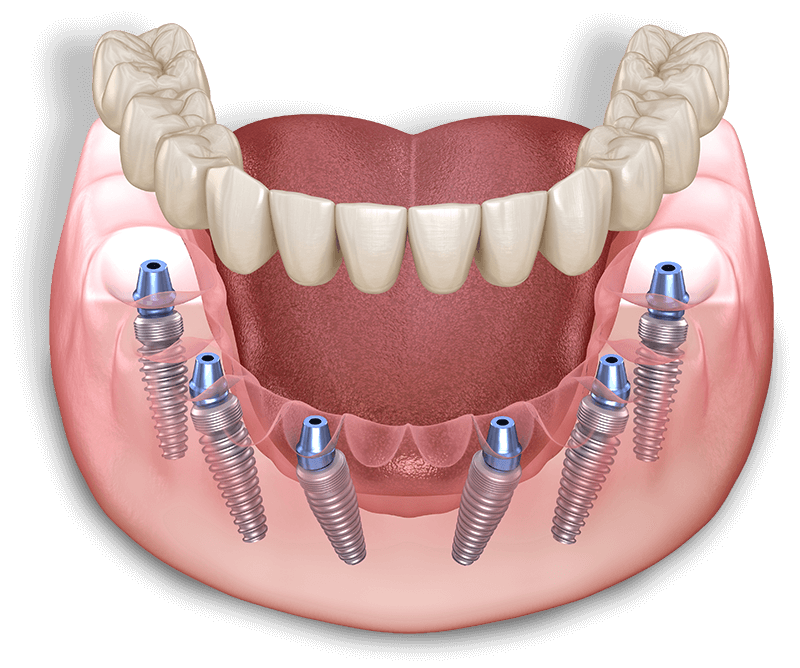

We now offer a Full Warranty on all Full Mouth Implant Treatments with a Permanent Zirconia Bridge! This gives you peace of mind to know that you are not only getting great value when you move forward with the treatment, but that this treatment will stand the test of time!